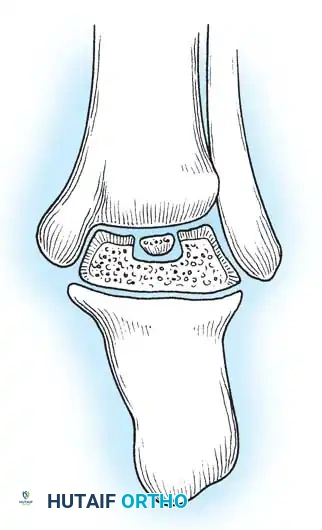

Fig. 33-204 Four types or stages of osteochondral fractures (osteochondritis dissecans of talus). Stage I, “blister”; stage II, elevated fragment but attached; stage III, fragment detached but still in crater; stage IV, displaced fragment.

Morphologically and etiologically, medial and lateral lesions differ significantly:

- Lateral Lesions: Almost exclusively caused by trauma. They are typically thin, wafer-shaped, and resemble acute osteochondral shear fractures. They are more prone to persistent symptoms and degenerative changes.

- Medial Lesions: While many are traumatic, a significant portion have no history of trauma (suggesting true osteochondritis dissecans or ischemic etiology). Medial lesions are typically deep and cup-shaped.

Fig. 33-205 Morphology of medial and lateral lesions. Lateral lesions are typically shallow and wafer-shaped, while medial lesions are deeper and cup-shaped.